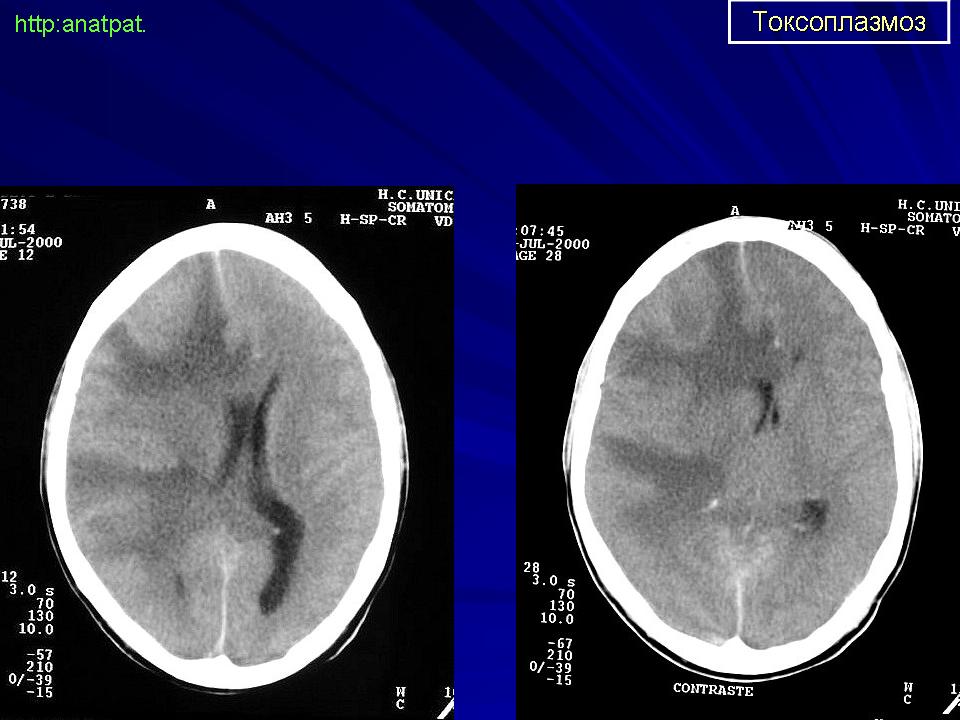

Церебральный токсоплазмоз.

Церебральный токсоплазмоз

http://www.uaz.edu.mx/histo/pathology/ed/ch_9c/c9c_toxo_ct_scan.htm

Токсоплазмоз

Neurotoxoplasmosis

Дифференциальная диагностика изображения